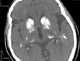

Craniosynostosis - intracranial calcifications

Craniosynostosis

Intracranial calcification